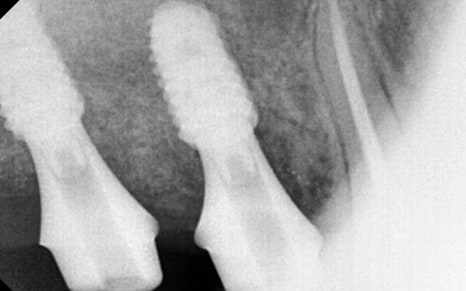

까다로운 유착 조직을 하나하나 박리하고,

상악동 점막을

손상시키지 않은 채로 거상에 성공,

동시에 명확한 위치에

임플란트를 식립하였습니다.

서울오브치과병원은

늘 상대 치아와 평행하게,

잘 맞물리는 위치에

임플란트를 식립하는 원칙을 지키고 있습니다.